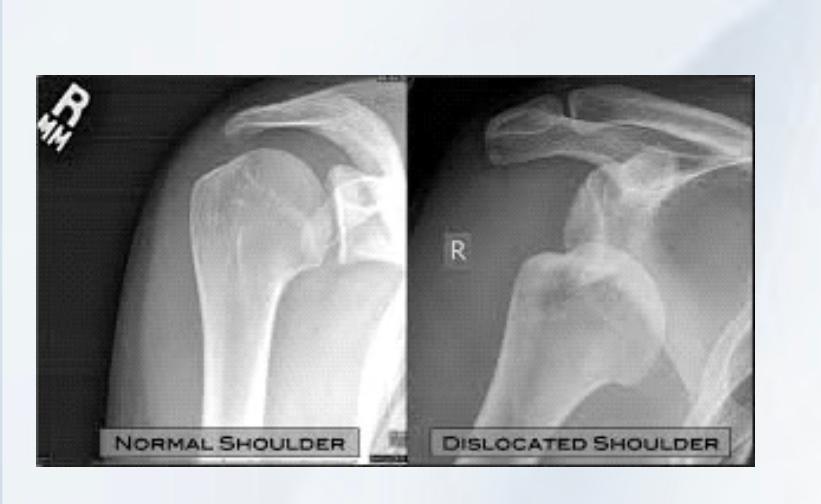

LUXAÇAO DO OMBRO

A luxação do ombro é a perda de contato dos ossos que compõe essa articulação, no caso o úmero e a escapular. Por ser a articulação do corpo humano com maior arco de movimento ela é mais suscetível a luxação, sendo a articulação mais deslocada no adulto. As principais causas da luxação são traumas no ombro ou então por frouxidão ligamentar. Radiografia é o primeiro exame a ser solicitado para se confirmar a lesão. Outros exames como a tomografia e a ressonância também são solicitados para a investigação de outras lesões. O tratamento imediato e a recolocação do ombro no lugar, através de manobras específicas. Alguns pacientes podem evoluir para um quadro de luxação recorrente do ombro, no qual a articulação pode sair do lugar com movimentos simples do dia a dia. Nessas situações o tratamento mais provável é o cirúrgico. O procedimento realizado na grande maioria das vezes é a artroscopia do ombro, entretanto alguns casos podem necessitar de cirurgia aberta ,